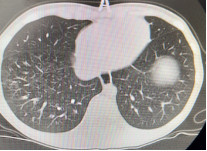

以下为呼吸专业典型病例分享:

图片2:气管狭窄后电切、球囊扩张、二氧化碳冷冻治疗